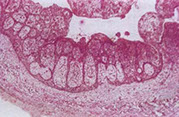

Necrotizing sialometaplasia of the palate with pseudoepitheliumatous hyperplasia (PEH)

Necrotizing sialometaplasia

Lobular coagulative necrosis of acini (glands); ductal metaplasia; PEH of the overlying squamous epithelium; mucous pooling and granulation tissue; fibrosis (inna late lesion)

- squamous metaplasia and hyperplasia of the duct system retains the duct system architecture

- inflam is probably caused by a reaction mucin released by necrotic glands

- is a reactive lesion secondary to infarct of salivary gland tissue, typically on the palate

Px: is a self-limiting condition, the act of the bx usually releases growth factors that lead to resolution